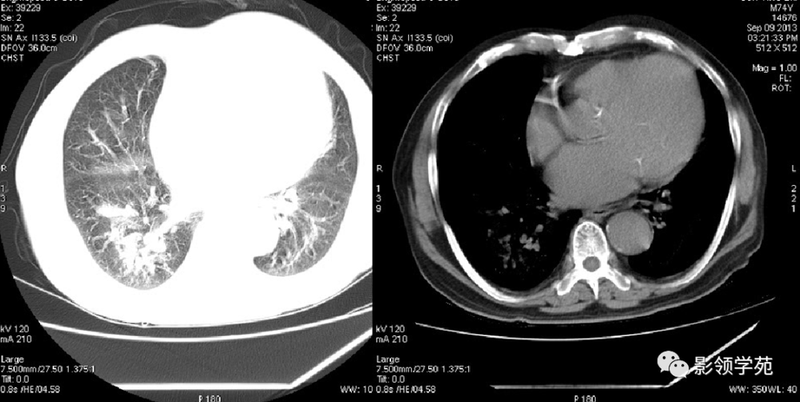

(1)较大含空洞性肿块,洞壁较厚,大于15mm,空洞外壁有分叶、毛刺,洞壁凹凸不平有壁结节,增强可见不规则强化,周围未见明显卫星病灶时,首先考虑周围型肺癌;癌性空洞洞壁一般肺门侧较厚,空洞多偏于外侧,伴有同侧淋巴结肿大更支持肺癌诊断。

(2)空洞病变发生于双肺上叶尖后段、下叶背段,病变周围可见点状、结节状及片状卫星病灶,洞壁组织无明显强化或有包膜线样强化时,考虑结核;结核球的空洞多位于病变的肺门侧,与引流支气管相同,洞内壁一般较光滑。

(5)肺内多发结节,由肉芽肿和炎症构成,较大结节发生空洞,多数结节边缘见有血管进入,则要考虑到肺韦格氏肉芽肿可能。